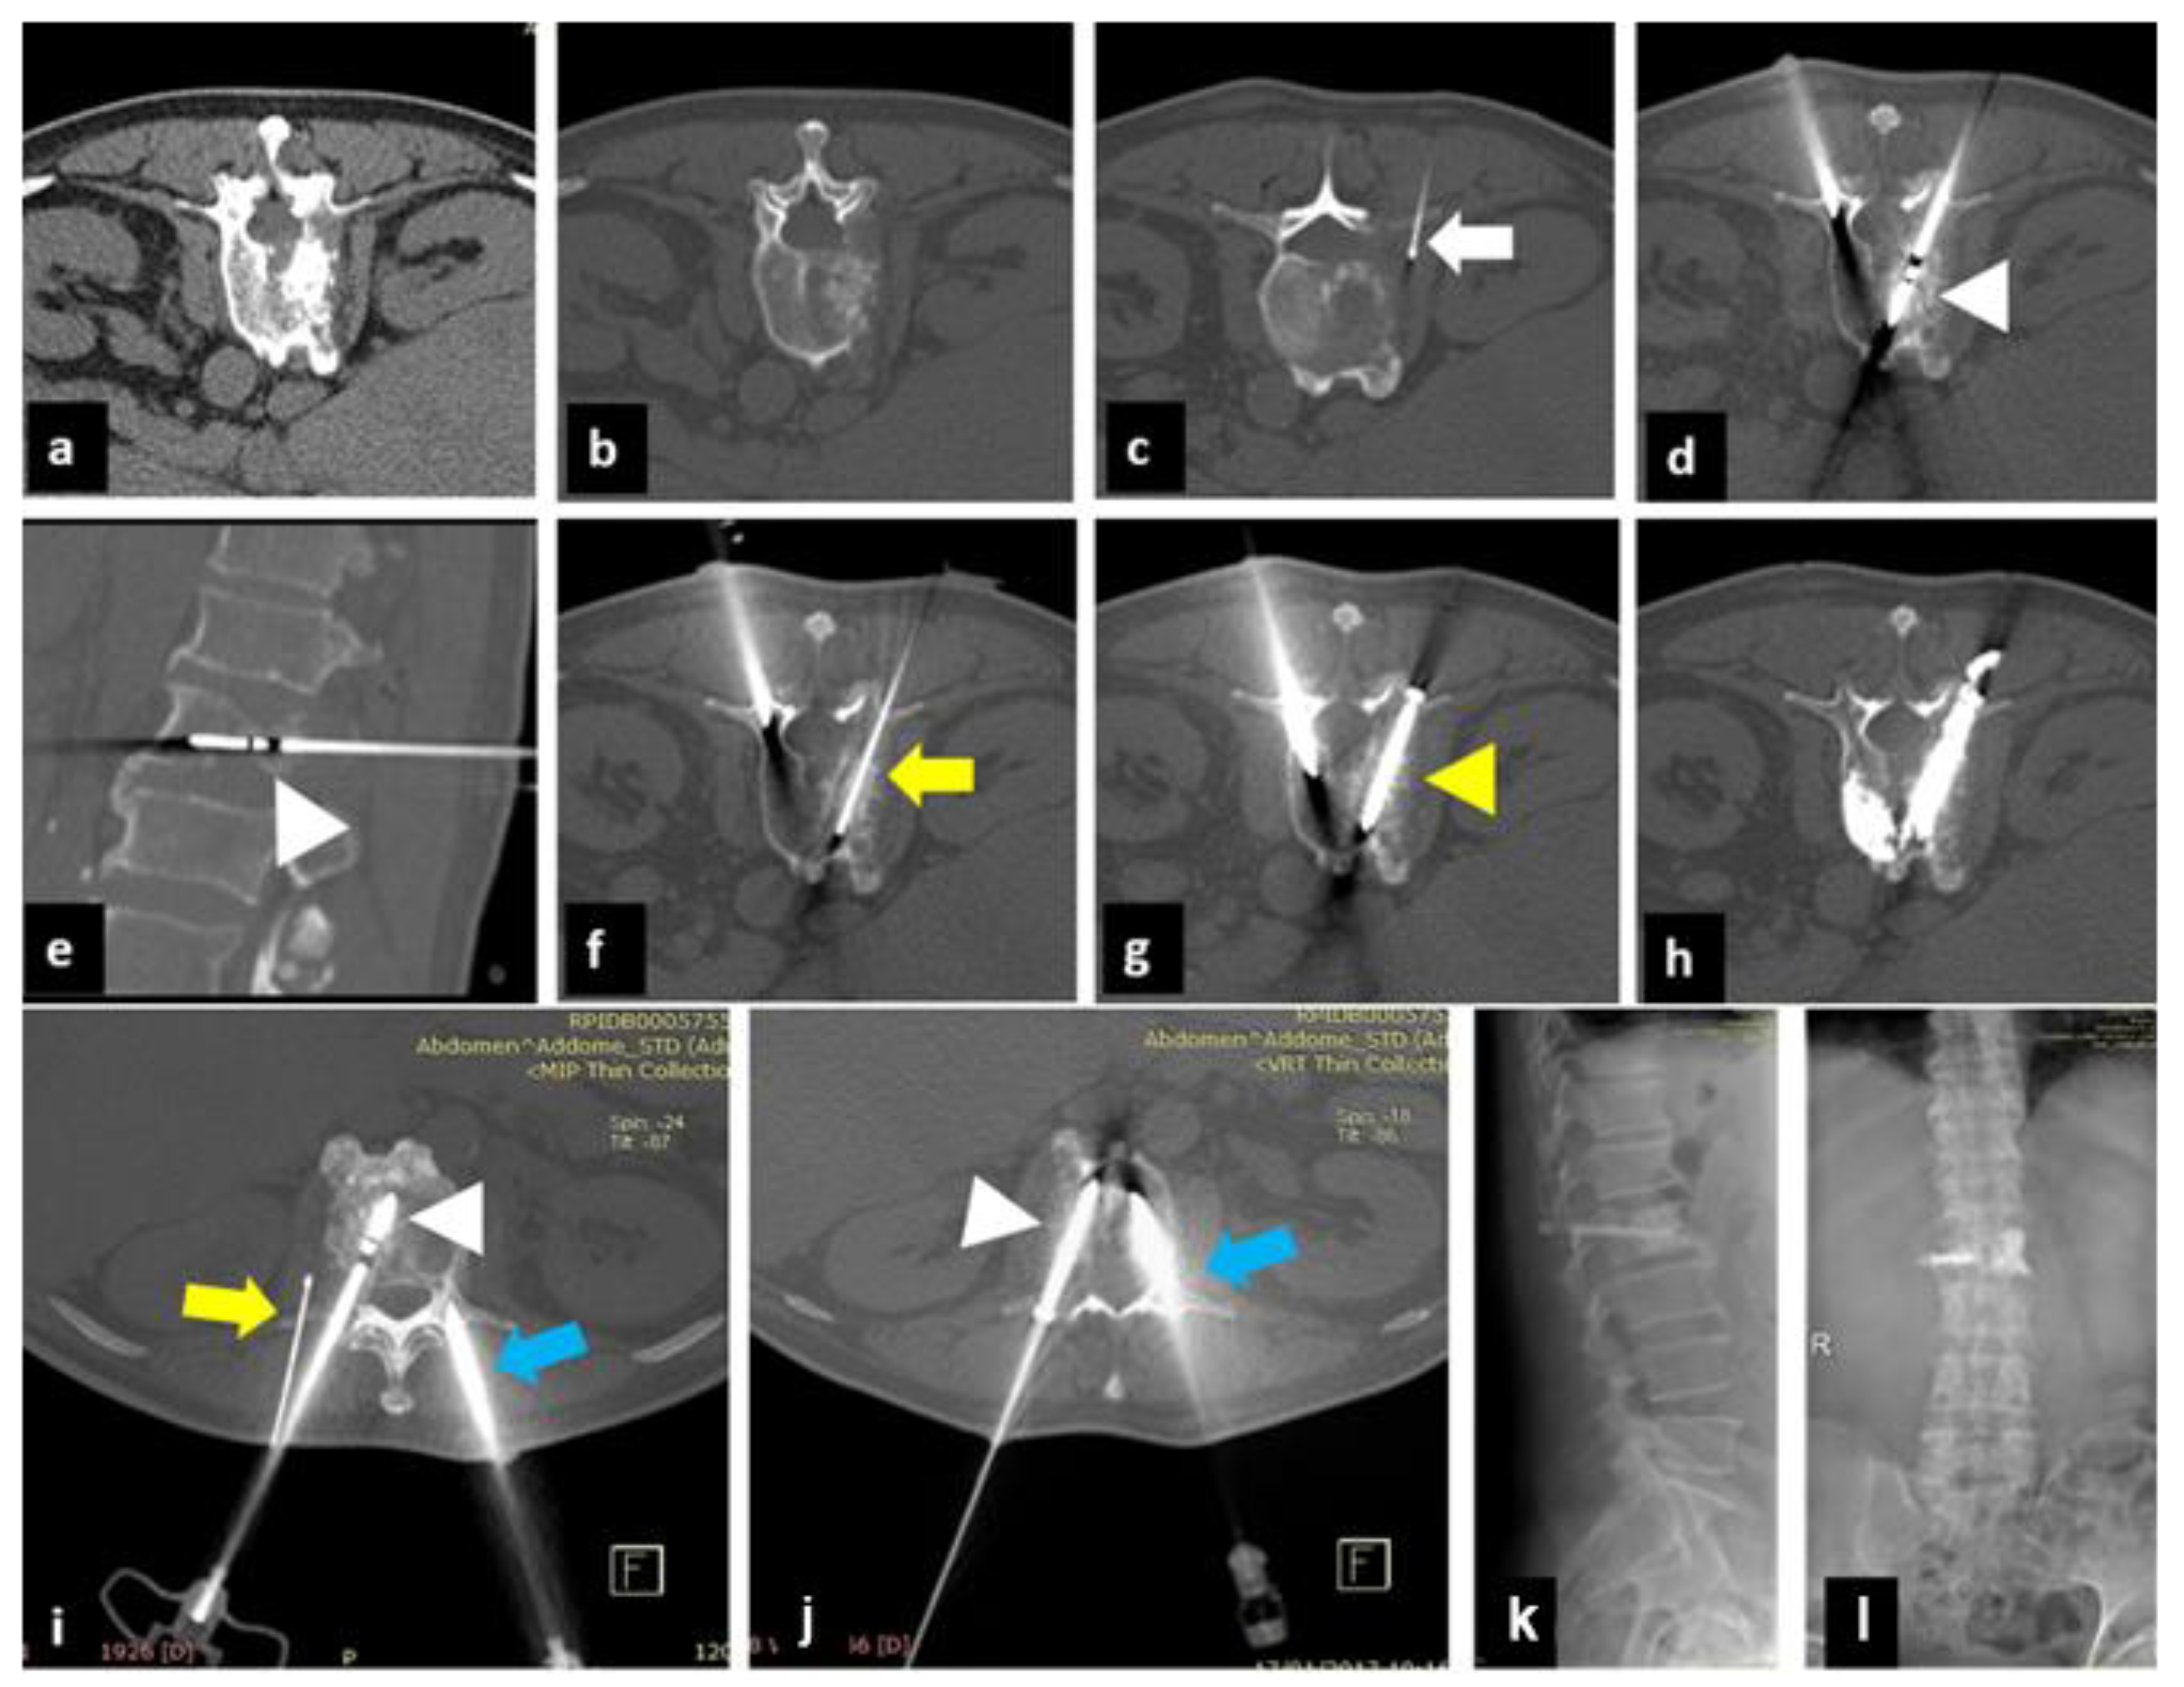

2. Materials and Methods

2.1. Treatment Technique

| 5 | 74 | SCLC | L1 | 1 | 1 | 8/4 | 4/2 | 2/2 |

| 6 | 50 | NSCLC | D10 | 2 | 2 | 6/3 | 3/2 | 0/1 |

| 7 | 84 | breast cancer | D11 | 1 | 2 | 7/3 | 1/2 | 1/2 |